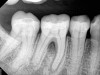

Fig 8. Cases treated by the continuous wave of condensation technique using gutta percha and epoxy resin sealer.

Figure 8

A version of warm vertical compaction, termed the continuous wave of condensation, is one of the most widely utilized obturation techniques19 (Figure 7 and Figure 8). This method involves placement of a single, tapered gutta percha cone fit to the same size as the master apical file with sealer, and downpacked with a controlled electric heat source. Based on the rotary instrumentation system used, either 04 or 06 tapered, ISO standardized apical size gutta percha cones corresponding to the final size and shape of the prepared canal can be placed with an appropriate sealer. A plugger heated to 200°F is introduced into the apical third of the root as determined by the working length to condense the apical portion of gutta percha. The heating element is turned off but left in place for an additional 5 seconds to allow slight cooling before a quick burst of heat. The heating element is removed with the coronal portion of excess gutta percha. Following this, the remainder of the canal space is filled using flowable gutta percha delivered via a motorized backfill device to the level of the chamber floor. This method can be hybridized with lateral compaction, in which spreaders are used to add accessory cones, when the shape of the canal does not allow for a tight fit of the ISO sizes of gutta percha points.